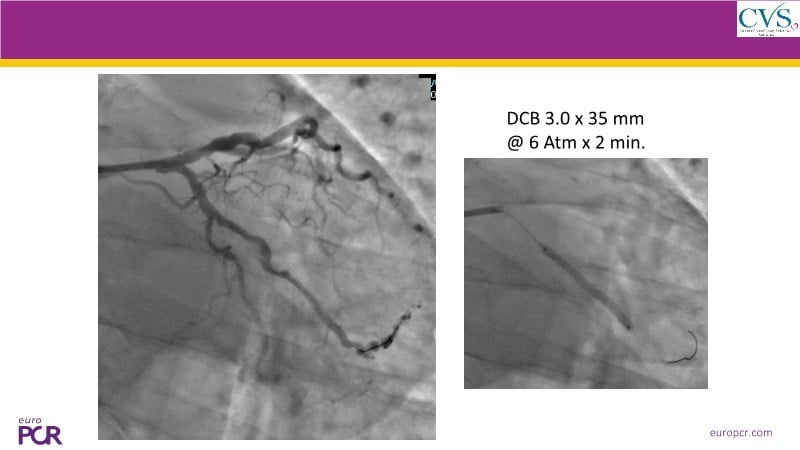

Discover how the next-generation RevoEdge high-pressure cutting balloon is transforming PCI with innovative design and proven clinical outcomes. This session presents a multicenter randomised trial and real-world case discussions, showcasing RevoEdge’s effectiveness in tackling resistant, complex lesions—including long, tortuous, and fibrotic cases. Learn practical tips, tricks, and intravascular imaging insights to optimize lesion preparation and improve patient outcomes. Don’t miss this opportunity to see how RevoEdge helps you cut through challenges and conquer PCI complexities.

- To explore the innovative design of RevoEdge: the next-generation high pressure cutting balloon

- To learn about the clinical benefits and tips and tricks of using RevoEdge high pressure cutting balloon in different types of complex lesions through case-based discussion